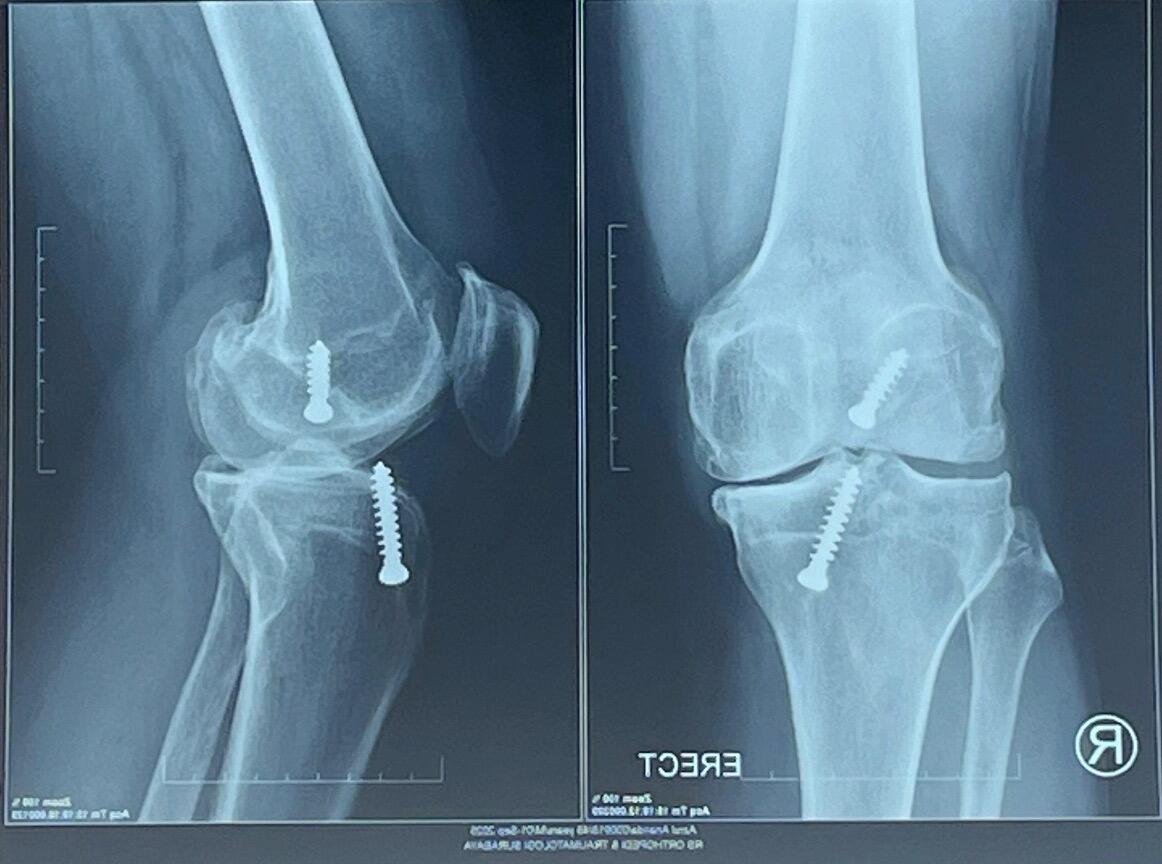

Pada Jumat, 12 Desember lalu, sebelum menjalani operasi ganti lutut/TKR (total knee replacement), saya hanya minta satu hal pada Theri Effendy, dokter yang akan melakukan prosedurnya. Saya minta tolong dua baut yang ada di dalam lutut kanan saya diselamatkan. Ingin saya simpan.

Dua baut titanium itu sudah menjadi bagian dari lutut saya selama 20 tahun. Sejak mengalami cedera sepak bola cukup parah di penghujung 2005.

Akhirnya MRI. Hasilnya: Anterior cruciate ligament (ACL) kanan putus total, meniscus sobek, dan ada bone contusion. Langsung operasi, tapi masih metode jadul. Dengan metode open patella, dengan menggunakan dua baut.

Tahun 2025 ini adalah ujung kesabaran saya tentang lutut ini. Hasil x-ray terakhir, sisi dalam lutut kanan sudah OA (osteoarthritis) grade 3-4.

Menurut Theri, saat lutut saya dibongkar, kondisinya memang parah. Istilahnya "rusak", bahkan "hancur". Meniscus alias bantalan sudah nyaris tidak ada, ACL juga praktis tidak berguna. Tulang-tulang rawan sudah banyak rusak, tulang-tulang muda bertumbuhan tidak aturan mengganggu di mana-mana. Khususnya di belakang lutut, membatasi gerakan menekuk ke belakang.